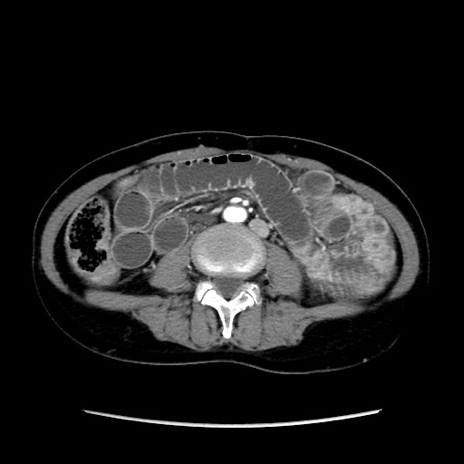

冠状断像

【症例】40歳代 女性

【主訴】上腹部痛、嘔気・嘔吐

【現病歴】約9時間前頃から急に上腹部痛、嘔気、嘔吐が出現。改善しないため救急要請。

【既往歴】子宮頚癌(広汎子宮全摘術、放射線療法)、腸閉塞

【身体所見】腹部:平坦、軟、腸雑音亢進、上腹部を中心に腹部全体に圧痛あり。

【データ】WBC 8400、CRP 0.03